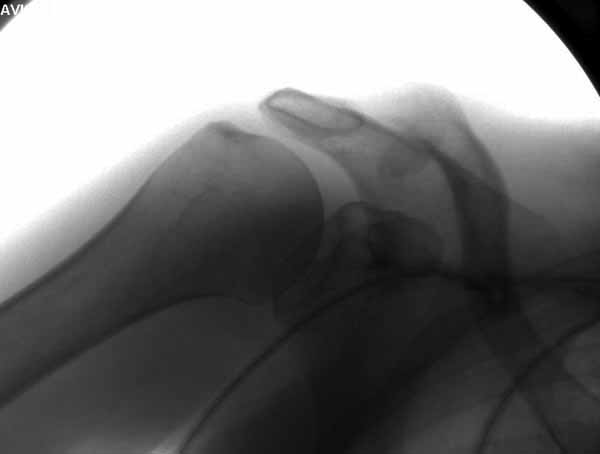

foto

2.JPG

foto 3

3.JPG

foto 4

4.JPG

foto 5

коллаж у меня не получился, пришлось отдельно рентгенограммы присоединить :-))

5.JPG

15KB (16356 bytes)